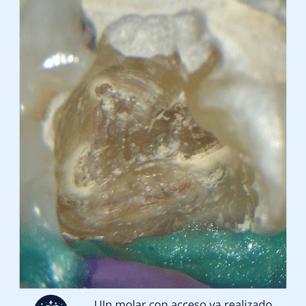

Acceso al Conducto: Se hace una apertura en la corona del diente para acceder al conducto radicular.

Localización y Remoción de

Calcificaciones: Se utilizan instrumentos especiales, como limas ultrasonicas, para localizar y remover las calcificaciones.